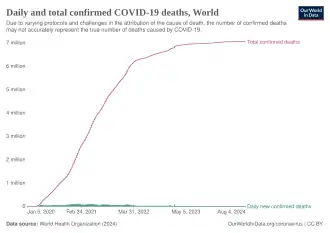

Total confirmed deaths over time

Total confirmed deaths over time -

![Total confirmed deaths due to COVID‑19 per million people[352]](./_assets_/World_map_of_total_confirmed_COVID-19_deaths_per_million_people_by_country.svg.png) Total confirmed deaths due to COVID‑19 per million people[352]

Total confirmed deaths due to COVID‑19 per million people[352]